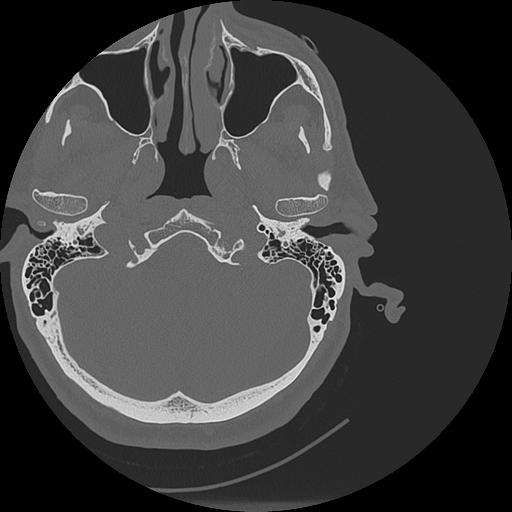

7 HUESO,,Vol,0.5,HUESO,,